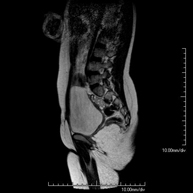

Prova diagnòstica no invasiva que consisteix en l'obtenció d'imatges d'alta definició anatòmica de la columna lumbar i sacre mitjançant l'ús d'un camp electromagnètic i ones de ràdio (amb un emissor i un receptor). No utilitza radiació ionitzant. Indicacions: traumatismes, ciàtica, hèrnies discals, tumors, infeccions - RM Mielografia

Prueba diagnóstica no invasiva que consiste en la obtención de imágenes de alta definición anatómica de la lumbar y sacra mediante el empleo de un campo electromagnético y ondas de radio (con un emisor y un receptor). No utiliza radiación ionizante. Indicaciones: traumatismos, ciática, hernias discales, tumores, infecciones. - RM Sacro-cóccix